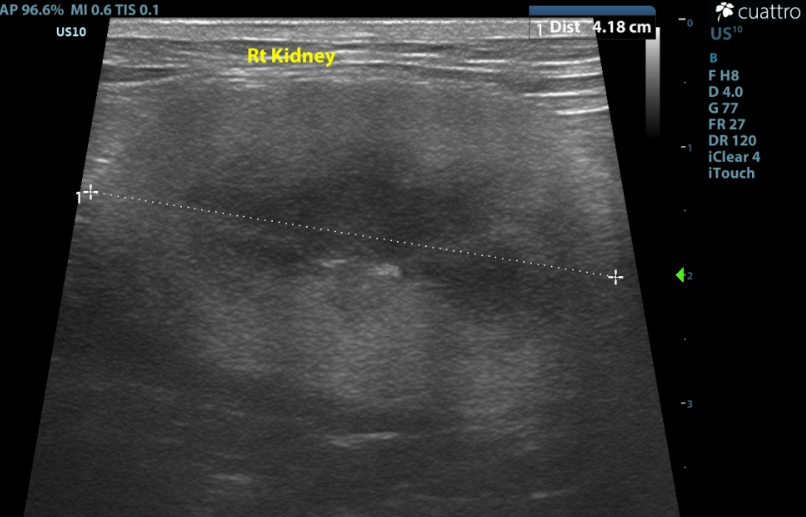

Kidneys ---Both kidneys have borderline to enlarged size (Lt/Rt =4.7 /4.1cm ) and normal shape with coarse moderately hyperechoic renal cortices which are disproportionately large. There is moderate loss of the corticomedullary junction distinction. No pyelectasia seen.

(normal renal size 3.2cm to 4.2cm; Renal Size in Cats, JAVMA, July 2005, Vo